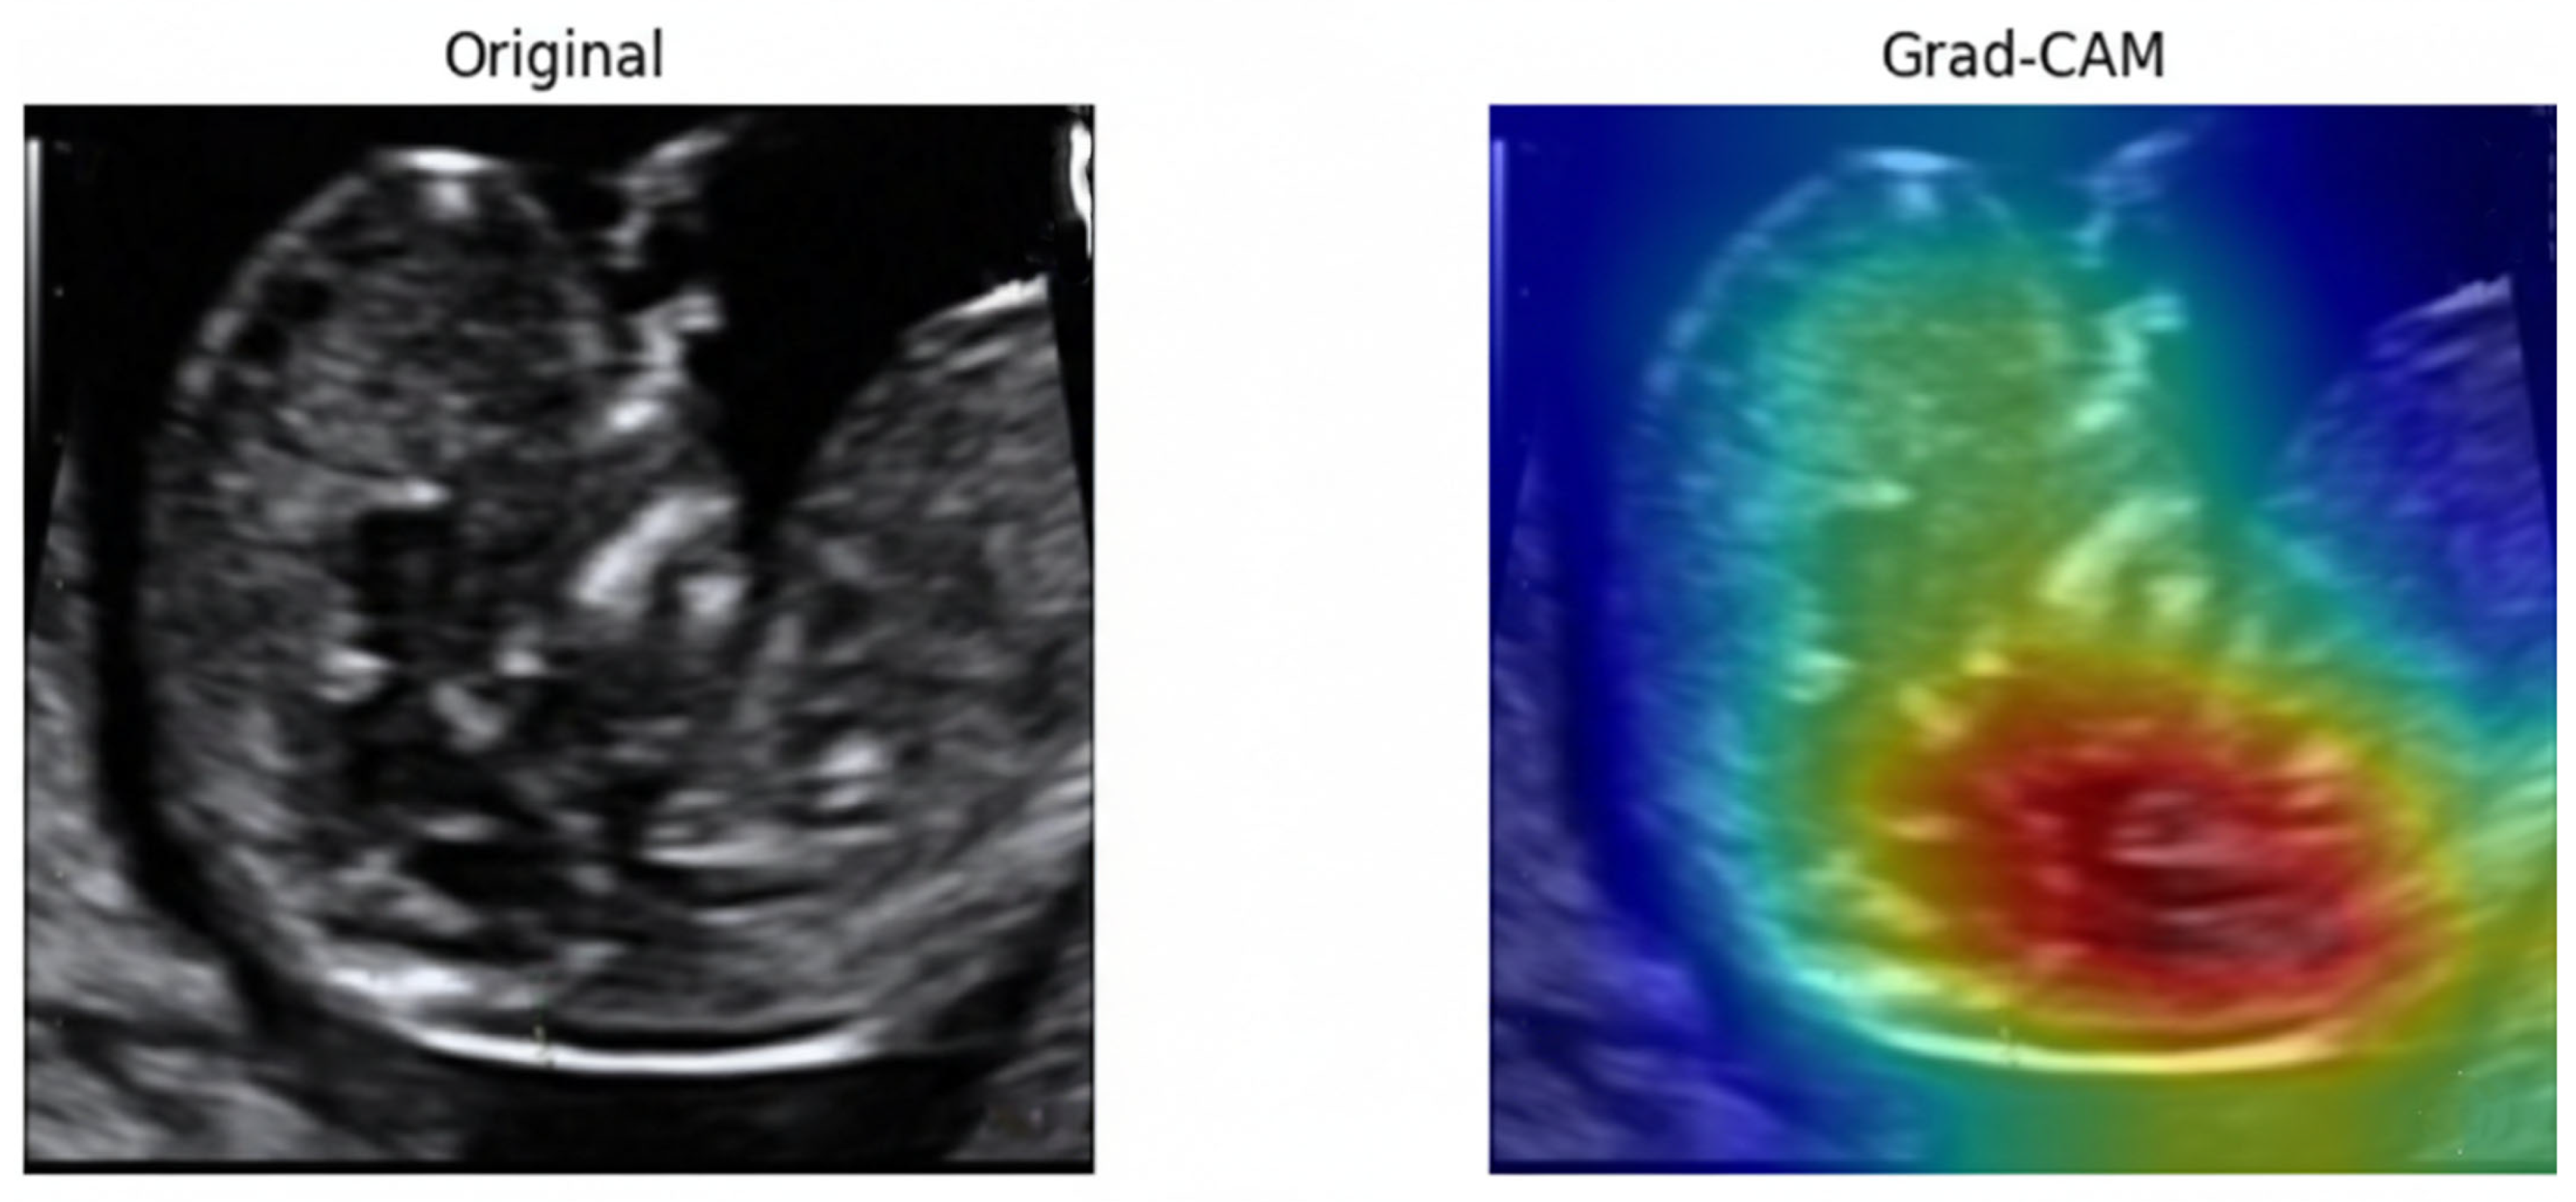

To examine the model’s decision-making process, Gradient-weighted Class Activation Mapping (Grad-CAM) [67]. As illustrated in Figure 25, the model consistently directed its attention to the fetal nuchal region—the clinically relevant anatomical structure used for NT evaluation. Warmer colors (red, yellow) indicate regions contributing most strongly to the classification output.

Figure 25.

Original ultrasound image and corresponding Grad-CAM heatmap.

The focused activation over the NT space confirms that the model learned meaningful, physiologically aligned representations rather than relying on irrelevant background textures. This explainability further supports clinical trustworthiness and transparency in automated NT image assessment.

In the first stage, image-quality assessment using DenseNet121 achieved superior performance compared to other widely used convolutional neural network architectures, including VGG, ResNet, EfficientNet, and Inception variants. The achieved accuracy of 0.94 and AUC of 0.986 demonstrate that DenseNet121 effectively discriminates between standard and non-standard NT ultrasound images, even when trained on a relatively limited dataset. This result is consistent with previous findings indicating that dense feature reuse improves performance in medical imaging tasks with limited data availability. Importantly, Grad-CAM visualizations confirmed that the model consistently attended to anatomically relevant regions around the fetal neck rather than irrelevant background structures, supporting the clinical plausibility of the learned representations.